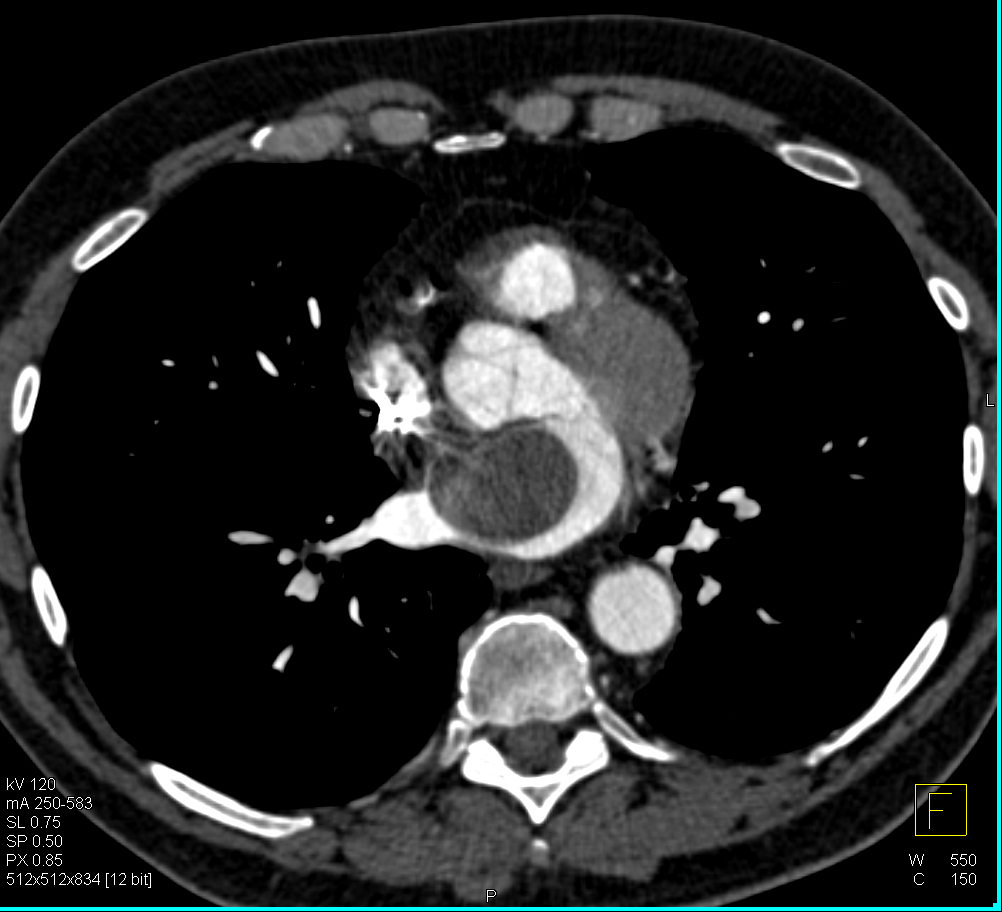

1) The most likely dx in this 50ish yr old male is?

4) The most likely diagnosis in this case is?

adrenal metastases

adrenal lymphoma

adrenal adenoma

adrenal pheochromocytoma